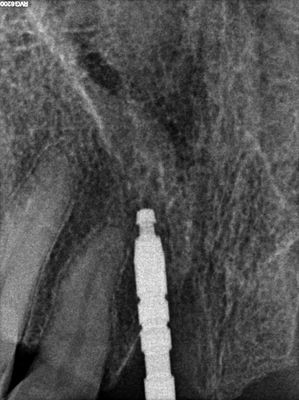

Atraumatic exo 11 and 22, some loss of labial plate, osteotomies underprepared, implants placed, sockets and buccal of 22 grafted with allograft, collagen membrane placed buccal of 22 socket.